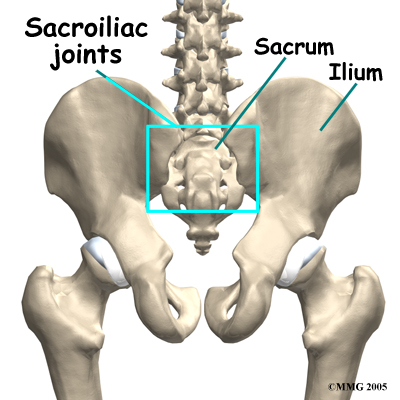

At the lower end of the spine, just below the lumbar spine lies the sacrum. The sacrum is a triangular shaped bone that is actually formed by the fusion of several vertebrae during development. The sacroiliac (SI) joint sits between the sacrum and the iliac bone (thus the name “sacroiliac” joint). You can see these joints from the outside as two small dimples on each side of the lower back at the belt line.

The SI joint is one of the larger joints in the body. The surface of the joint is wavy and similar to the way Legos fit together. Very little motion occurs in the SI joint. The motion that does occur is a combination of sliding, tilting and rotation. The most the joint moves in sliding is probably only a couple of millimeters, and may tilt and rotate two or three degrees.